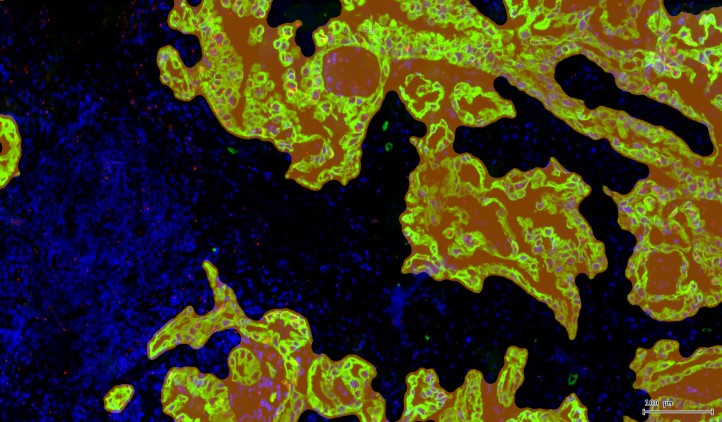

例如下图:橙色-肿瘤区域

3、相关性分析:发现目标之间的内在关联

例如:判断不同蛋白表达水平的相关性